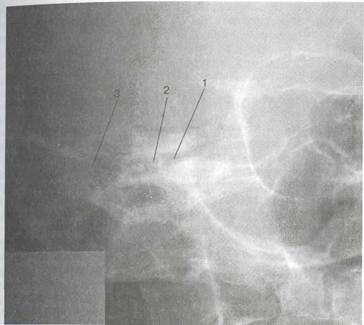

Рис. 1.12. Обзорная рентгенограмма височных костей в укладке по Шюллеру.

1 — височно-нижнечелюстной сустав; 2 — наружный слуховой проход; 3 — внутренний слуховой проход; 4 — сосцевидная пещера; 5 — периантральные ячейки; 6 — ячейки верхушки сосцевидного отростка; 7 — передняя поверхность пирамиды.

Боковая обзорная рентгенография височных костей по Шюллеру (рис. 1.12). С ее помощью выявляется структура сосцевидного отростка. На рентгенограммах хорошо видны пещера и периантральные клетки, четко определяются крыша барабанной полости и передняя стенка сигмовидного синуса. По этим снимкам можно судить о степени пневматизации сосцевидного отростка, видна характерная для мастоидита деструкция костных перемычек между ячейками.